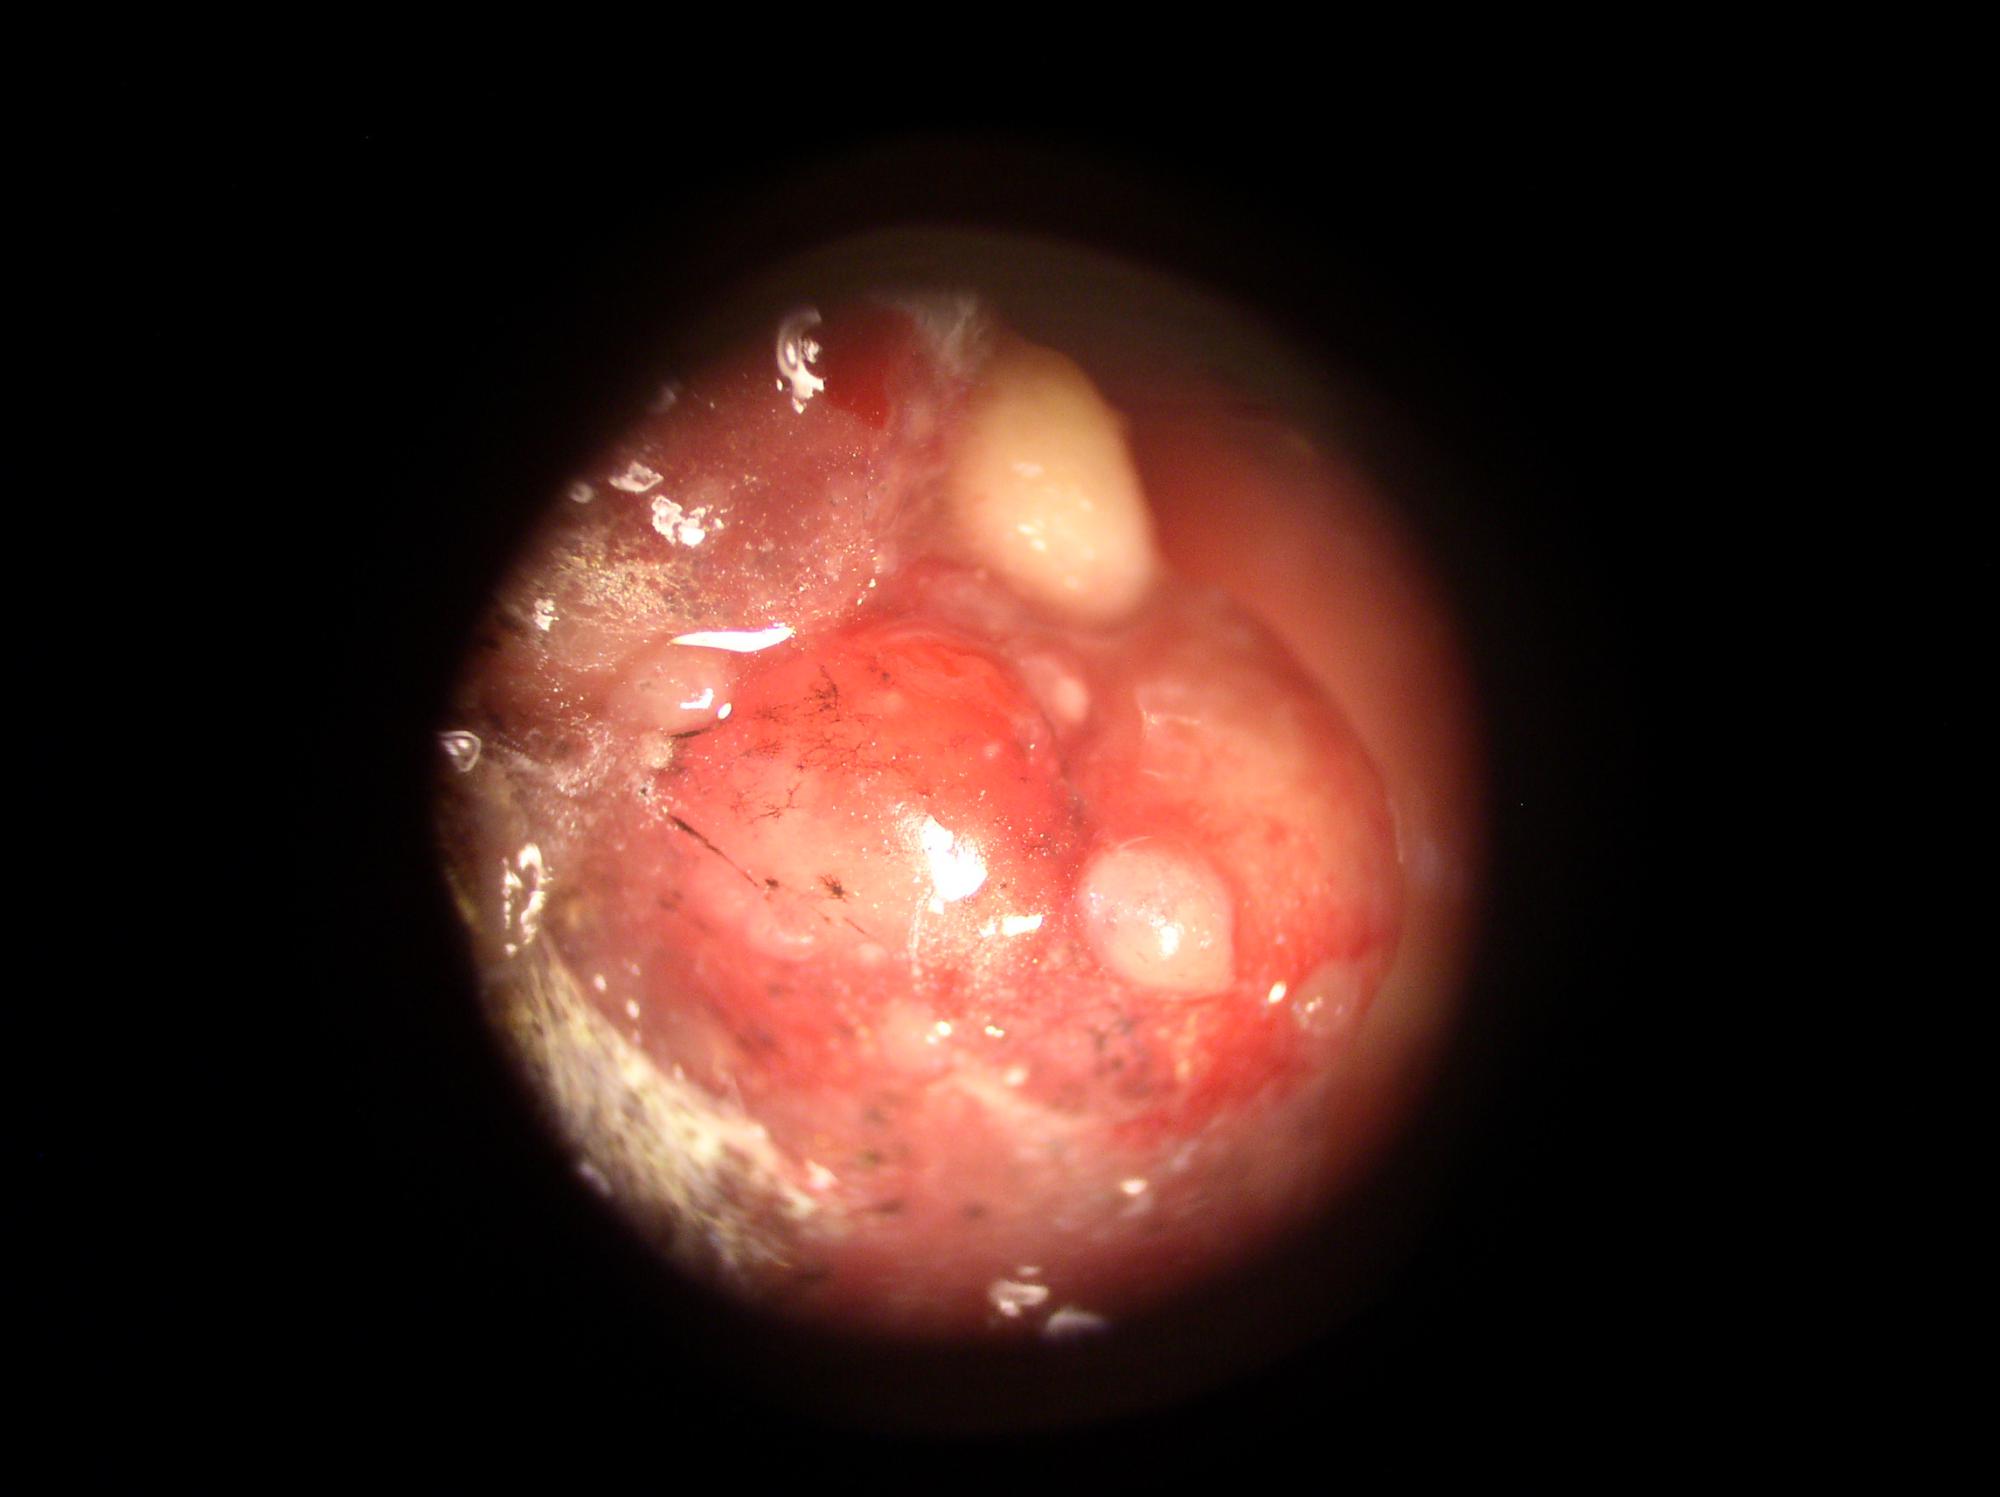

Вот фото, которые удалось сделать дома.

На фото:

1,2,6 - целые капсулы.

Они блестящие, покрыты некой плёнкой.

3-5 - разрезанные капсулы.

Внутренняя структура нопоминает мокрый хлебный мякиш.

В этом "мякише видны чёрные включения, как кусочки грязи.

7,8 - кожа возле жабер.

На коже видны участки без кожи.

9,10 - внутренние органы.

Справа вверху видна капсула.

Она там и была.

И видны чёрные сеточки.

11 - общий вид.

Видны многочисленные капсулы.

больше похоже на жировики. При большем увеличении не микроскопировали?